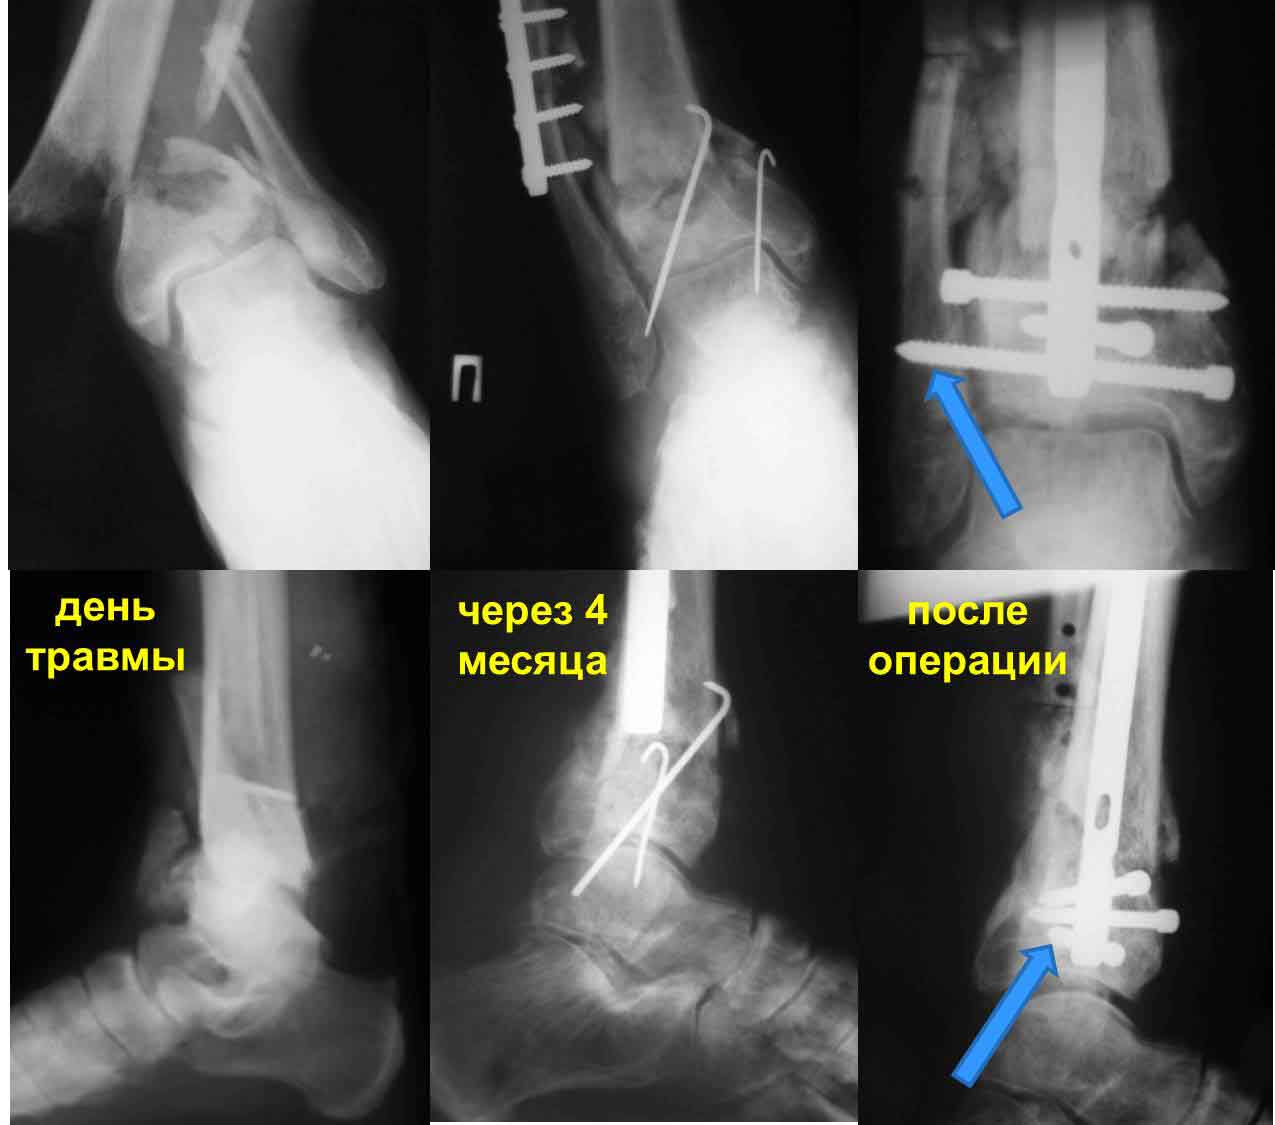

Частота ложных суставов и повторных смещений костных отломков после оперативной стабилизации переломов пилона доходит до 30%. Каждый, кто занимается лечением таких повреждений, наверняка сталкивался с такими осложнениями. Однако лечить такие осложнения в моральном,  да и в оперативном плане проще, чем свежие переломы пилона (особенно Ruedi III), поскольку к этому времени становится более или менее понятной судьба голеностопного сустава. Если в достаточной мере владеете блокированным остеосинтезом, то самым оптимальным вариантом, с моей точки зрения, будет следующий. С переднемедиального и латерального доступов выполнить поперечную остеотомию большеберцовой и малоберцовой костей в плоскости параллельной плоскости голеностопного сустава на расстоянии около 3 см от самого сустава. Это минимальное расстояние, которое позволит расположить три блокирующих винта стержня. Важен выбор самого стержня. В данном случае больше всего подходит стержень ChM, имеющий на дистальном конце помимо отверстий в сагиттальной и фронтальной плоскостях и отверстия под углом в 45 градусов, причём на минимальном расстоянии друг от друга. Остетомию и последующую репозицию костных отломков мы выполняем в репозиционном спицевом аппарате. Стержень антеградный. В данном случае не вижу никаких оснований в применении ретроградного стержня, проходящего через здоровый подтаранный и через голеностопный сустав с его до конца неопределённой функцией. Образовавшийся дефект по переднемедиальной поверхности должен быть заполнен костным трансплантатом. Пример похожего случая из нашей практики - в приложенном файле.